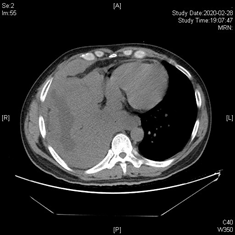

今年3月份,已经持续发热伴咳嗽将近2月有余的小张,曾被其他医院诊断为转移性肺低分化腺癌,已到晚期,但小张接受传统化疗后,发热、咳嗽、气促等症状仍没有改善,他抱着最后一丝希望辗转就诊我院。

入院后,呼吸与危重症医学科医师们综合分析病情,认为治疗的突破点应该是积极寻找可能存在的肺癌驱动基因,再次选择合适的病灶部位进行肺穿刺活检是关键。

在肺癌一体化诊疗模式下,放射科、病理科等相关的多学科专家很快就汇集一堂,共同探讨患者病情,最终确定最佳活检部位,最佳基因检测方法及范围,难题迎刃而解!根据新的基因检测报告,呼吸与危重症医学科医师们重新做出诊断,为右下肺腺癌,小张接受新的靶向药物治疗后体温即降至正常,咳出灰白色坏死物,咳嗽、气促减轻,家属激动的说:将近2个多月来,终于听他说想要吃一些好吃的!太感谢医生们了!

1月后复查胸部CT,肺部病灶及胸膜病灶显著缩小,现患者病情已改善出院。